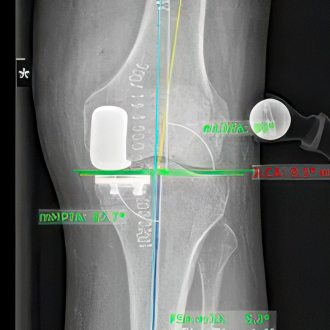

Knieendoprothetik

Dank roboterassistierter Kniechirurgie lassen sich Implantate besonders präzise einsetzen und die Funktion des Gelenks nachhaltig verbessern.